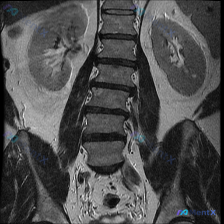

用户一开始先提了“脊柱侧弯(Scoliosis)”,这是腹部MRI的T2加权冠状位。

- 双肾大小形态还行,但左肾(图右侧)中下部有个类圆形的T2高信号,边界清,信号均匀,跟尿液差不多

- 集合系统没扩张,腹膜后、盆腔也没见明显肿块